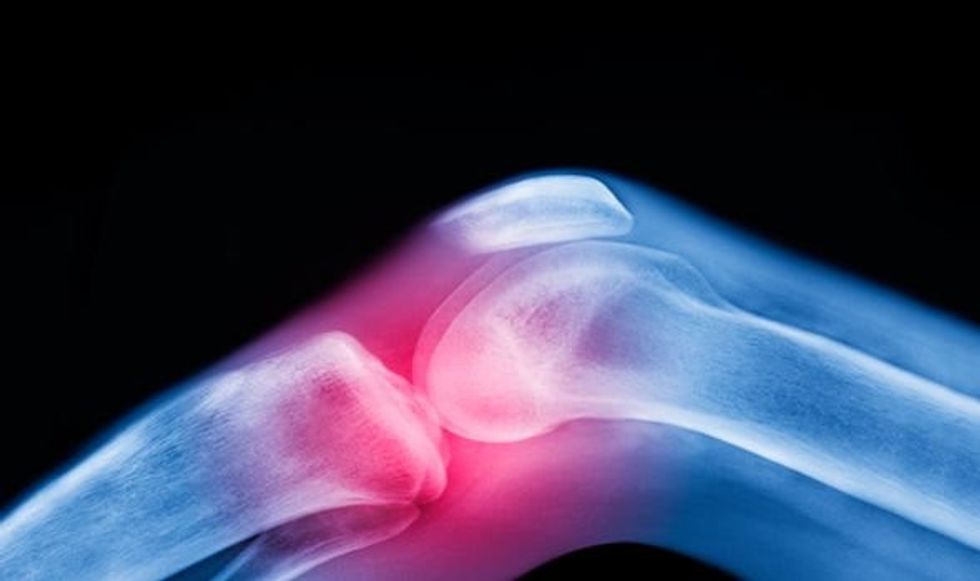

Dy aktivitetet të cilat e rritin rrezikun e osteoartritit të gjunjëve (Foto)

Sipas ekspertëve të ndryshëm, gjuri është një nga nyejt më të prekur nga osteoartriti, transmeton Telegrafi.

Simptomat e osteoartritit përfshin dhimbje, zë kërcitje, ënjtje të mëdha, etj.